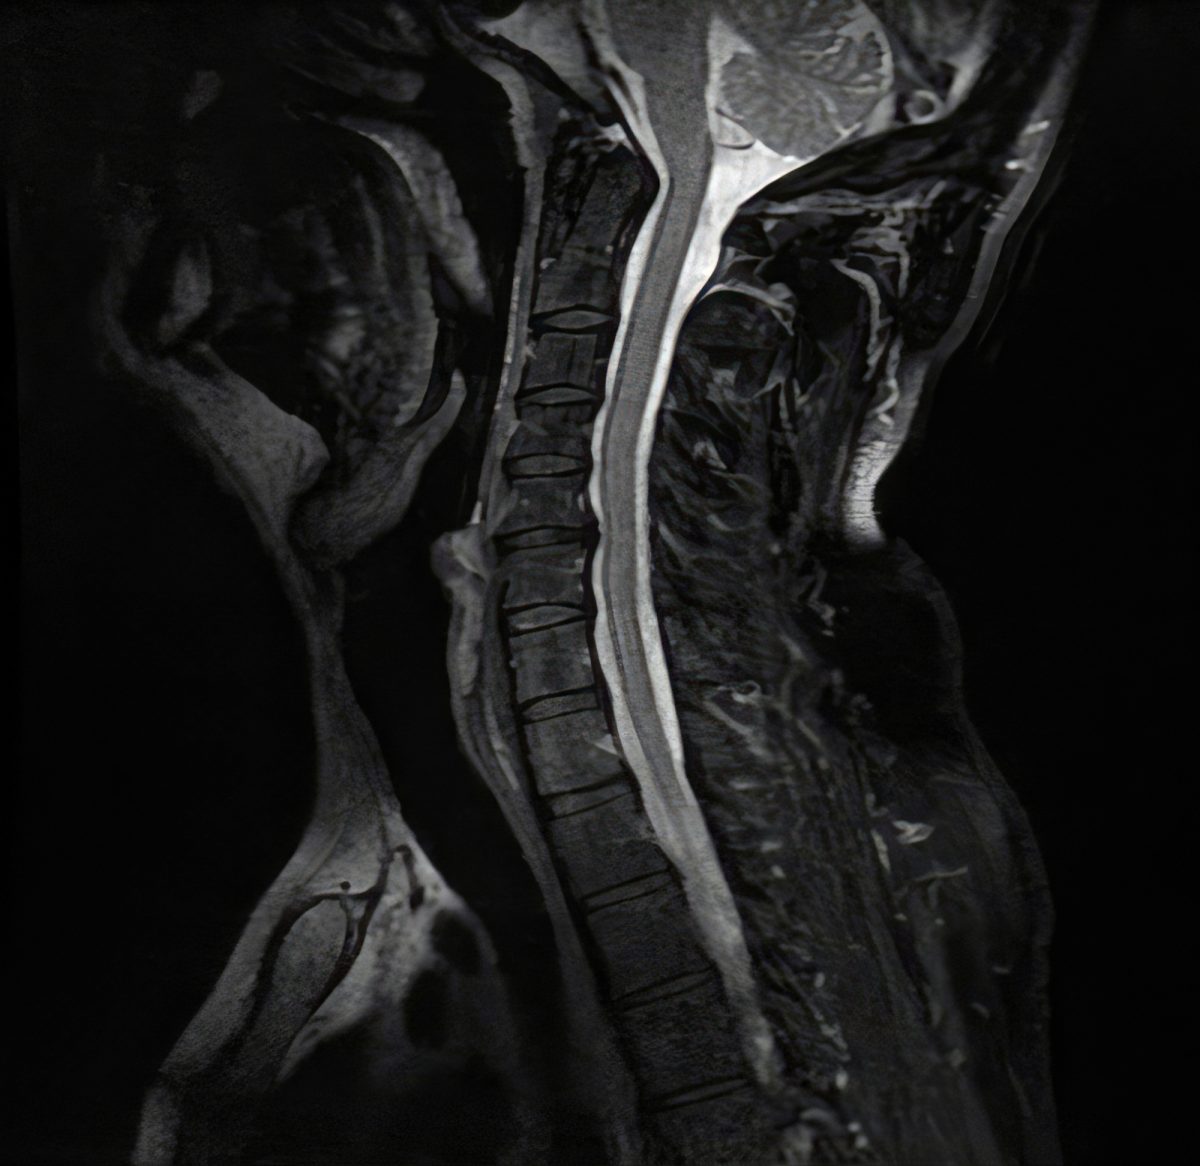

La catégorie « Chirurgie cervicale » regroupe l’ensemble de nos articles et pages consacrés aux pathologies et traitements chirurgicaux du rachis cervical. Vous y trouverez des informations détaillées sur les différentes affections touchant la région du cou, telles que l’hernie discale cervicale, la myélopathie, la cervicarthrose ou les traumatismes, ainsi que sur les innovations en matière de prise en charge : prothèse discale cervicale (arthroplastie), arthrodèse, microchirurgie, techniques mini-invasives, indications, déroulement des interventions et suites opératoires. Cette section vise à informer et accompagner les patients et leurs proches dans leur parcours de soins, en présentant de façon claire et actualisée les options de chirurgie cervicale les plus modernes, permettant de soulager la douleur, préserver la mobilité et optimiser la récupération fonctionnelle.